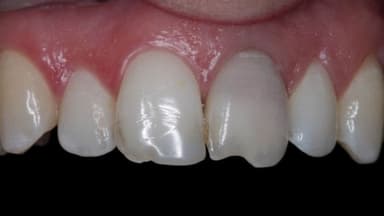

– Bảo vệ răng: Phương pháp này giúp bảo vệ răng khỏi sự tiến triển của sâu răng. Từ đó, răng sẽ được bảo vệ, lấy lại sự khỏe mạnh.

– Tái tạo răng: Vật liệu trám cung cấp một lớp bảo vệ cho răng. Từ đó, răng có thể được tái tạo lại cấu trúc răng bị tổn thương.

– Đảm bảo tính thẩm mỹ: ật liệu trám có thể được lựa chọn để phù hợp với màu sắc và hình dạng tự nhiên của răng. Nhờ vậy, chúng ta sẽ đảm bảo được tính thẩm mỹ răng miệng.